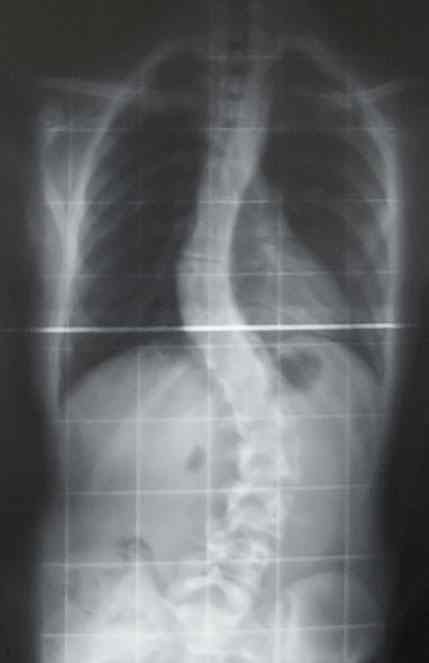

Fizjoterapeuta Jacek Białek przyznaje, że wady postawy to duży problem wśród dzieci i młodzieży. Wykryć je można już w przedszkolu.